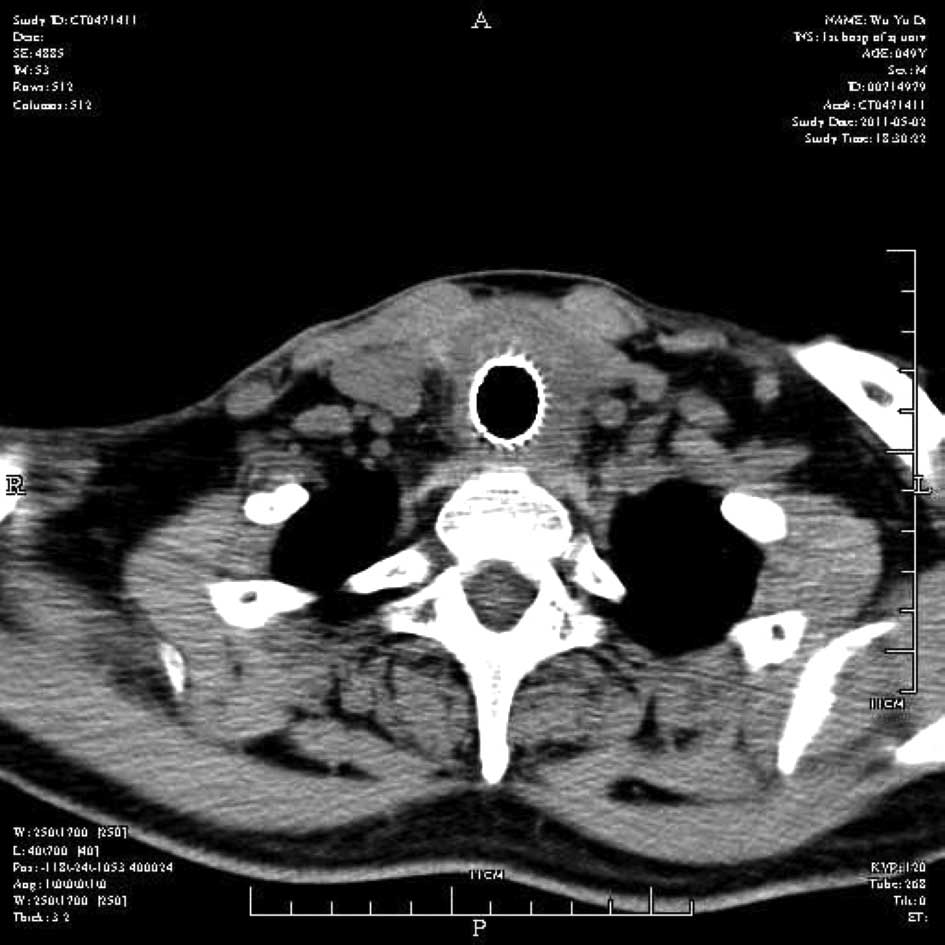

Emergency management of a patient with severe airway obstruction resulting from poorly differentiated thyroid carcinoma: A case report

We present a case of a life-threatening almost complete airway obstruction resulting from poorly differentiated thyroid carcinoma in a 48-year-old male. Airway obstruction may lead to unexpected mortality by suffocation and patients with poorly differentiated thyroid carcinoma usually have a fast deterioration and fatal outcome. In the case presented, we describe a safe and effective treatment strategy. Assisted by femoro-femoral cardiopulmonary bypass oxygenation, a tracheal stent was implanted successfully. Following surgery there were no complications, and chemoradiotherapy resulted in the relief of obstructing symptoms and improved the quality of life of the patient. This case indicates that femoro‑femoral cardiopulmonary bypass provides adequate oxygen support to undergo further management and that tracheal stent implant is an effective emergent measure to relieve severe airway obstruction in patients with poorly differentiated thyroid carcinoma.

Figure 1

Figure 2

Figure 3

Figure 4

Figure 5

Figure 6